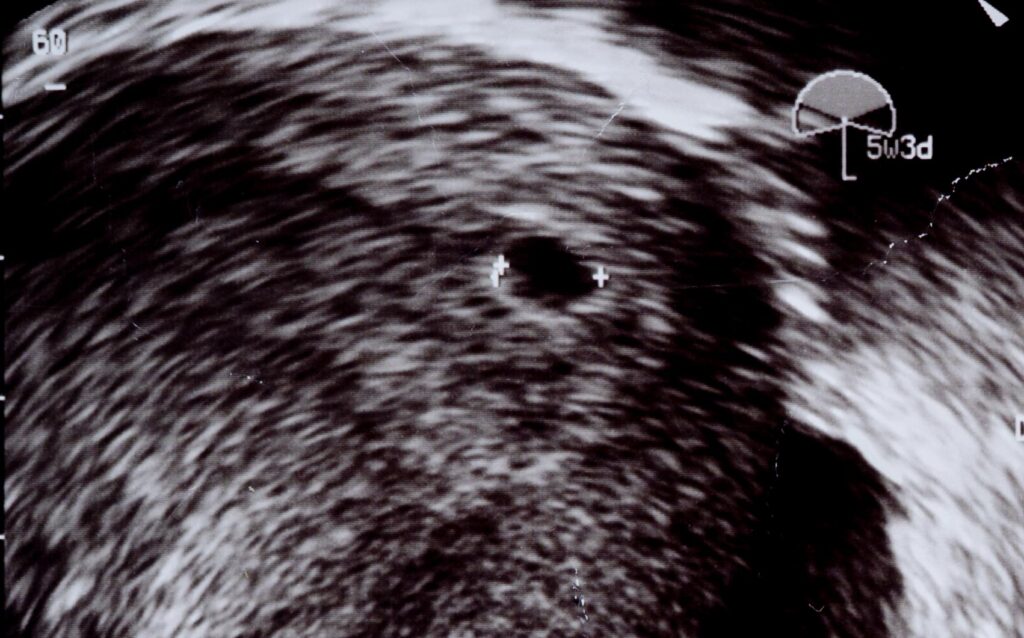

zwischenleere is a photobook and web project, created as my bachelor project, that makes visible the emotional and physical phases of miscarriage — before, during, and after the loss.

It responds to the fact that, despite their frequency, miscarriages are often socially silenced, which can leave those affected feeling isolated. Through repetition, contrast, emptiness, and the gradual reduction of formally similar motifs, the project translates the processual nature of grief into a visual language. The small, handheld format of the photobook creates a quiet, protected space for those affected. A complementary website transfers the reduced design into the digital realm and additionally offers space for interviews, personal testimonies, and further information.